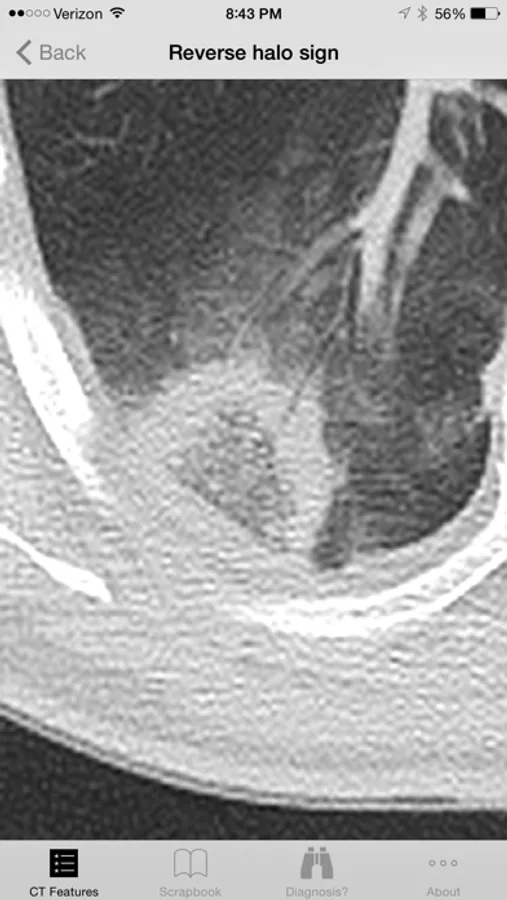

Introducing the Lung CT Field Guide app, an excellent resource for a wide-range of physician specialists, in particular radiologists and pulmonologists. One of the critical steps in interpreting a lung CT is identifying and appropriately describing imaging findings in the lung. Review and explore lung CT images and color graphic illustrations of the fundamental patterns of lung disease on CT. Play with an experimental diagnosis engine that will try to suggest a differential diagnosis list to consider with any number and combination of lung CT findings! Includes over 100 carefully curated CT images and color graphic illustrations.

· Over 60 prototypical lung CT images, organized by: increased attenuation findings, decreased attenuation findings, miscellaneous findings, craniocaudal distribution, and axial distribution